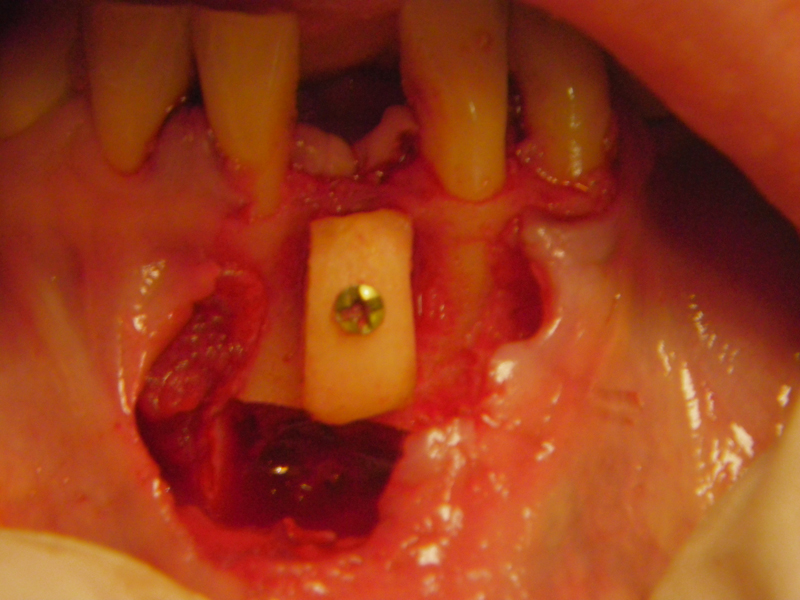

- Stage I: Implant placement/Sealing Screw

- Stage II: Implant uncovered healing cap

- Alveolar Ridge Augmentation

- Bone grafting – autogeneous, alogenic, xenogenic

- Blockgraft

- Fixation (plate, screws, wire)